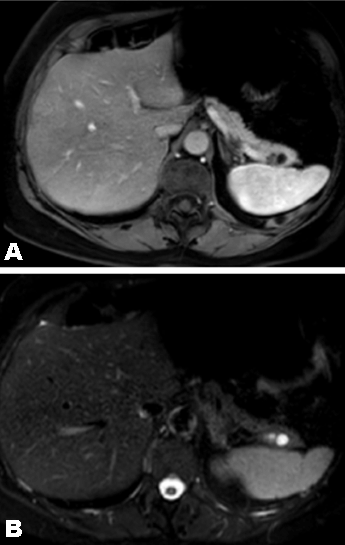

Clinical examination on admission revealed healthy looking women, comfortable, abdomen soft and no abdominal masses palpable. Blood tests including lipase, CEA and CA 19-9 were normal. Computed tomography scan and magnetic resonance imaging (MRI) scan showed a 19-mm cystic multi loculated lesion in the tail of the pancreas which was initially thought to be a serious cystadenoma. We decided to follow-up the lesions with MRI scan in three months’ time because of atypic characteristics of the lesion. Magnetic resonance imaging (MRI) at three month showed 24 mm cystic loculated lesion (increasing in size comparing to the last CT scan), well demarcated with a thick and contrast enhanced septa (Figure 1). No infiltration to the surrounding structure and no communication with the main pancreatic duct were described. Endoscopic ultrasound showed a 25-mm cystic lesion with same characteristics as on MRI scan and particularly did not find intramural nodule (Figure 2). For technical reason the puncture biopsy was not possible.

Figure 1:(A,B) Magnetic resonance imaging scan showing cystic lesion multi-lobulated located in the tail of the pancreas hypointense in T1, hyper intense in T2 with enhancement of the wall after gadolinium injection.

In computed tomography scan, hemangiomas are strongly contrast enhancing in the arterial phase, peripheral irregular enhancement with central non-enhancement in venous phase, and progressive filling-in during the delayed phases [5]. Pancreatic hemangiomas appear in the CT scan as well demarcated cystic lesion enhanced in the arterial phase with no communication with main pancreatic duct. The enhancement in the arterial phase is not found in all reported cases of pancreatic hemangioma. This is explained by the slow blood flow due to the presence of AV shunting. On MRI scan it appears as a lobulated, hypo-intense mass in T1-weighted images, and shows moderate hyperintensity signal in T2-weighted image [1][2].